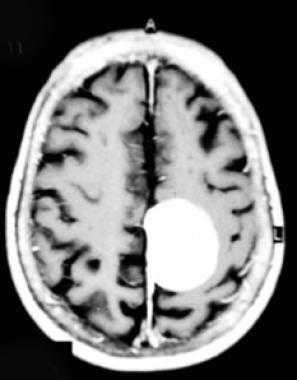

Тот же пациент. Внутрижелудочковая менингиома. Аксиальная Т2-зависимая МРТ, поперечная и сагиттальная Т1-зависимые МРТ с контрастированием.